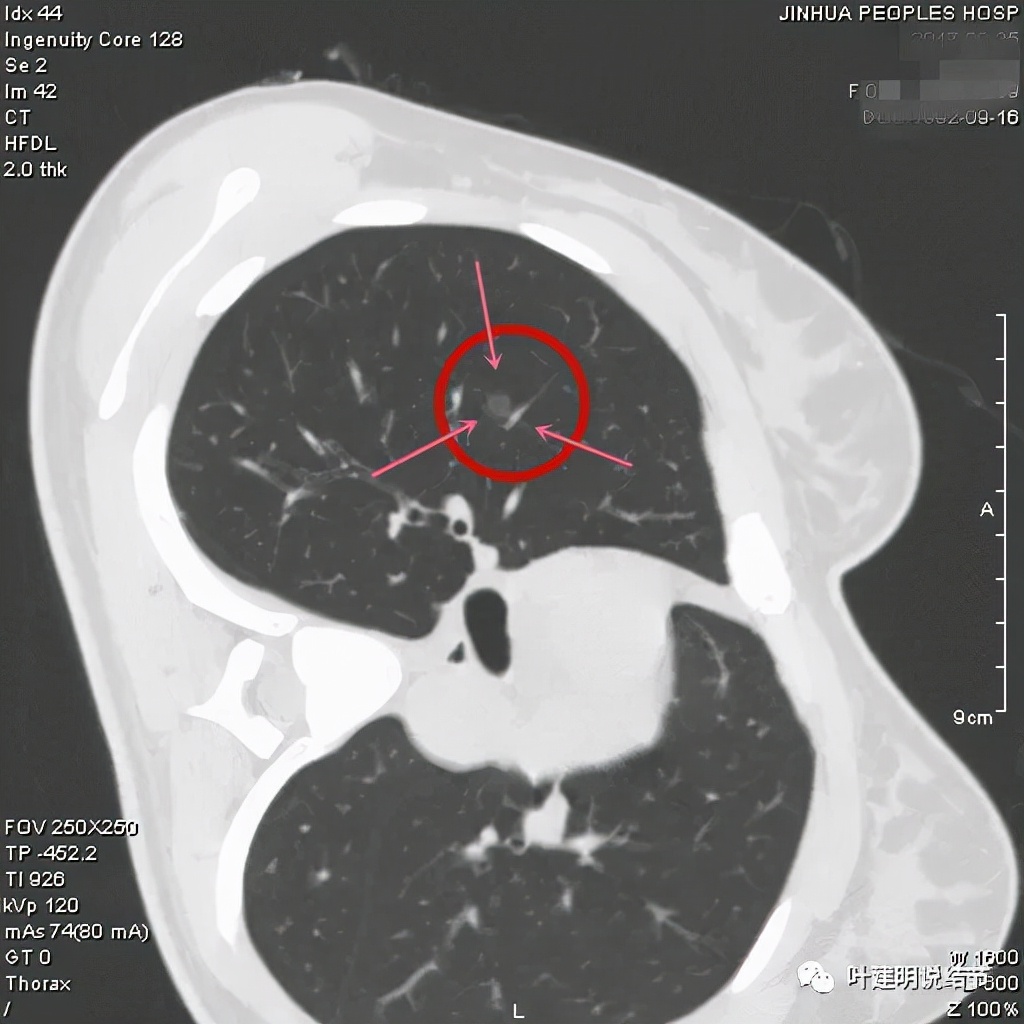

上图示病灶内部有高密度点状成分(粉色箭头所指)

同样示内部点状高密度,瘤肺边界清,密度显乱

上图显示混合磨玻璃结节,中间点状高密度区域,边上有微小血管征

上图示病灶边缘磨玻璃成分有的区域密度过低(绿色箭头),事后回头来看,磨玻璃部分的密度过低,不容易是浸润性腺癌,而更符合原位腺癌

上图示瘤肺边界处显模糊(砖色箭头),病灶内部仍是有偏高密度的点状成分

上图层面也显示病灶边缘欠清,有些模糊,虽总体轮廓还是比较清晰

从以上靶扫描图像上看,给人的印象是肿瘤范畴的结节,是混合磨玻璃结节,但磨玻璃部分的密度偏低,有的边缘显模糊,中间有点状高密度,也有微小血管进入,应该至少微浸润性腺癌可能性大。持续存在已经2月余,位置又还靠边上的,可考虑手术切除。下面再来瞧瞧后处理重建的图像: